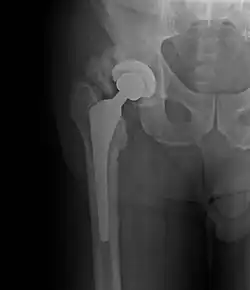

Ossification hétérotopique de la hanche